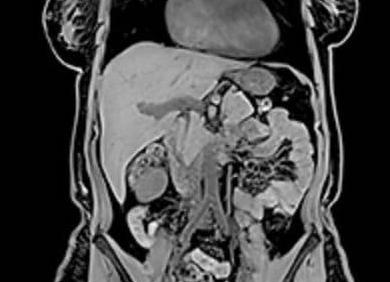

МРТ исследование является одним из самых современных методов изучения организма человека, которое широко используется при диагностике разных патологических состояний головного мозга. Благодаря ей можно увидеть любой орган послойно, а также очень точно оценить состояния структуры мягких тканей. Этот вид томографии является безопасным, качественным и высокоинформативным диагностическим исследованием.